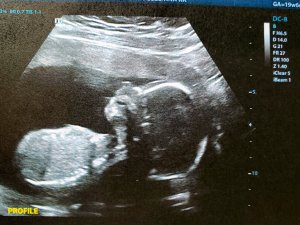

I’m now 20 weeks; halfway there.

Though I still haven’t felt any movement (not uncommon), the baby was incredibly active during my ultrasound yesterday. I clearly saw, thanks to the technician pointing it out, its wee legs kicking all over the place.

But enough about me, y’all want to see baby’s latest glamour shot.

I told the technician I didn’t want to know the gender, even though I do, so she didn’t even look. I held strong, my friends. I held strong! βπΌ

Baby is now 6.5 inches from crown to rump, roughly the size of a banana.

Baby sleeps and wakes at regular intervals, and could even be sucking its thumb – which I did until I was about four or five years old!

Since it’s now time for soup, Tylenol, and some more sleep, I’ll leave you with snapshots of my tenant’s spine, foot, and hands.